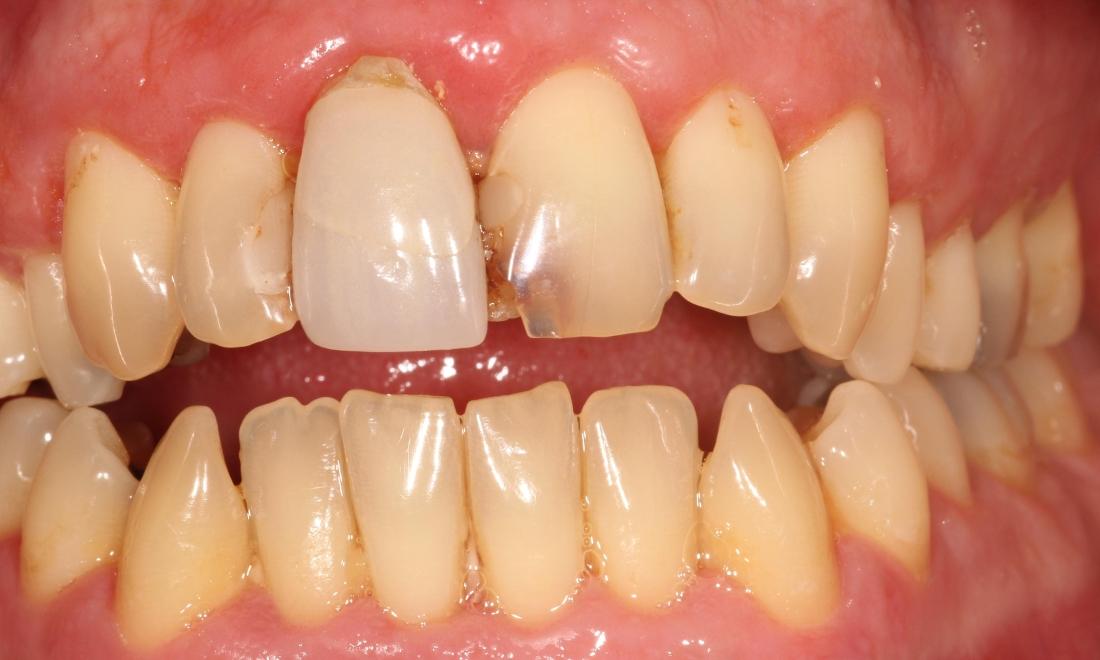

This patient presented with gross decay in the front teeth. We matched a good shade, removed the decay and restored the teeth with crown coverage.